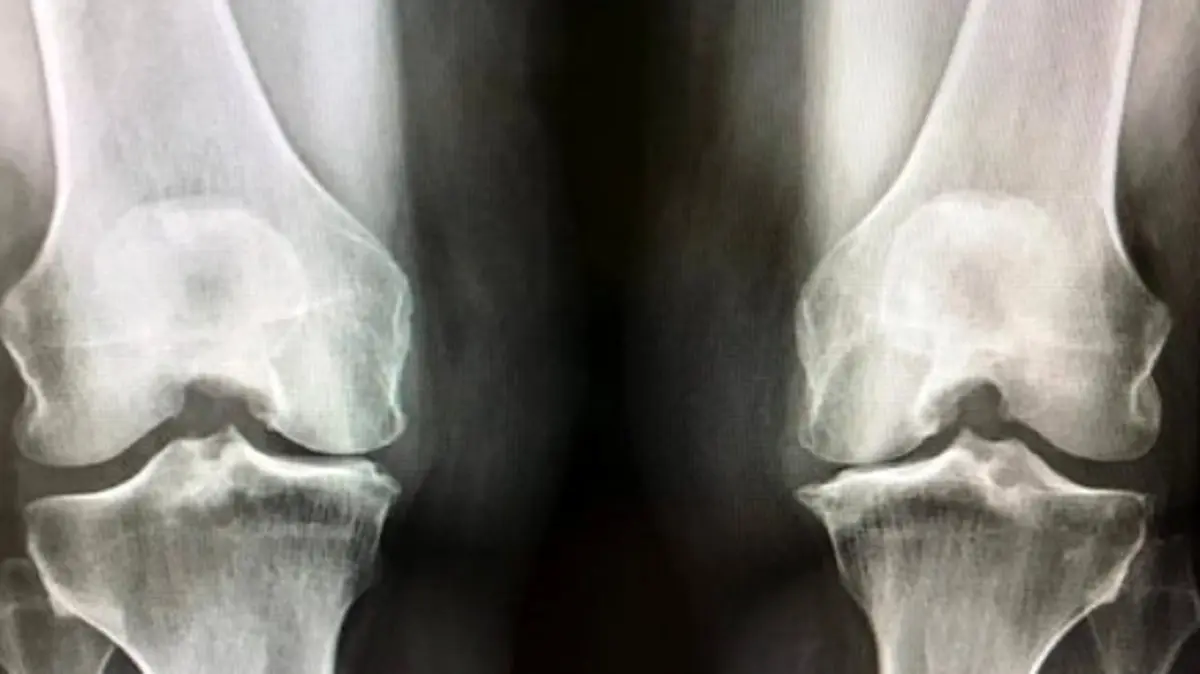

به گزارش رکنا، دکتر منصور مرادی، متخصص ارتوپدی در کردستان، اعلام کرد که آرتروز زانو به عنوان تحلیل رفتن غضروف میان دو استخوان شناخته میشود. این موضوع با افزایش سن، وزن بیش از حد، و روش زندگی نادرست ممکن است شکل بگیرد. یکی از عمدهترین دلایل این بیماری، پیشرفت سن است که با آن، تحلیل رفتن غضروف شدت میگیرد. همچنین، افزایش وزن و سبک زندگی ناصحیح نیز خطر ابتلا به آرتروز را میافزاید.

دکتر مرادی تاکید کرد که در صورت بروز زانو درد، مراجعه به پزشک و انتخاب تصمیمات درمانی مناسب، از اهمیت زیادی برخوردار است. متأسفانه، هیچ داروی کاملاً مؤثری برای درمان آرتروز موجود نیست و این وضعیت ممکن است به جراحی تعویض مفصل منجر شود.

با پیشرفتهای پزشکی در زمینه تعویض مفصل، افراد میتوانند بعد از جراحی به زندگی روزمره بازگردند. بهترین زمان برای این جراحی در بالای 60 سالگی است، هرچند در موارد خاص ممکن است در سنین پایینتر نیز انجام شود.